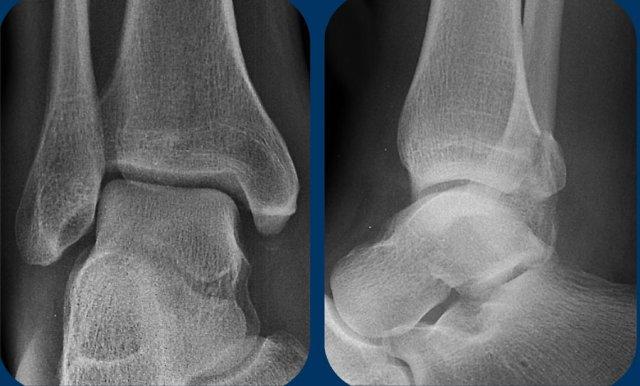

Hãy phân tích các hình ảnh này. Bạn có thể cần nhấp vào để xem ở kích thước lớn hơn.

Câu hỏi đầu tiên: Đây là gãy xương Weber A, B hay có thể là Weber C? Sau đó hãy cố gắng xác định giai đoạn và đánh giá xem cổ chân ổn định hay không ổn định.

Bạn có thể xem các hình ảnh tiếp theo để đọc phần thảo luận về các hình ảnh này.

Cuộn qua các hình ảnh.

Đây là gãy xương Weber B giai đoạn 4, thuộc loại không ổn định.